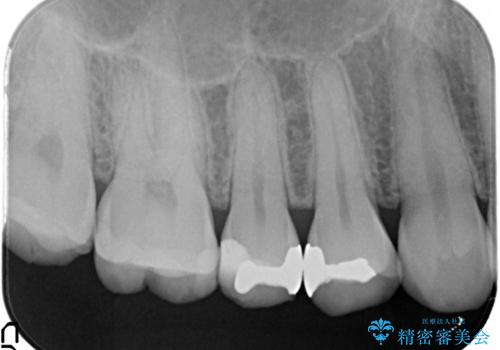

- 金属の詰め物を外して、セラミックインレーを入れたいと来院された患者様です。

奥歯に虫歯も認め、3歯の治療を来院回数2回で終了で終了しています。

当院でのセラミックインレーはすべてe-maxと呼ばれる高強度セラミックにて製作されます。

また、製作方法もプレスと呼ばれる方法を用いることで精度を高めています。